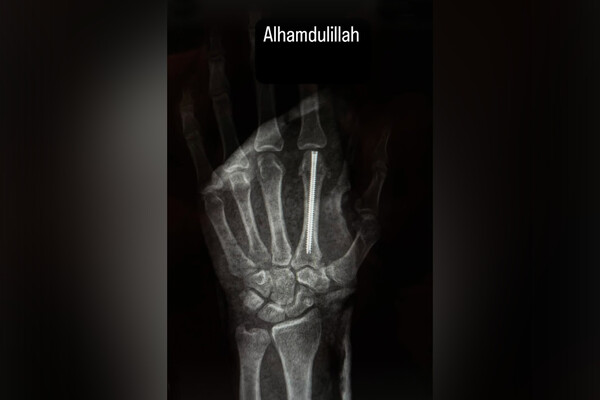

Брат Хабиба показал результат операции, где ему вставили штифт в руку

Боец Нурмагомедов вставил штифт в руку после поражения в титульном бою UFC

Российский боец Абсолютного бойцовского чемпионата (UFC) Умар Нурмагомедов на своей странице в Instagram (владелец компания Meta признана в России экстремистской и запрещена) показал результаты операции, которую был вынужден перенести из-за перелома руки, полученного в бою с чемпионом промоушена Мерабом Двалишвили.

На рентгеновском снимке можно увидеть, что Нурмагомедову вставили штифт в кисть левой руки. Боец получил перелом руки по ходу первого раунда поединка.